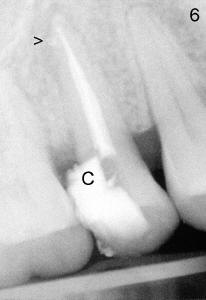

After removing DO caries and enlarging the access, it becomes obvious that there is a missing buccal canal (Fig.3 B). There is purulent discharge from the buccal canal in the beginning of the debridement. Fig.3 photo is taken after the buccal canal is fully shaped with rotary files (final file: 30/.06). Arrowhead points to the original lingual orifice with gutta percha. The RCT retreat is initiated on emergency basis. There is not enough time to remove the lingual gutta percha. More importantly, there is leakage of sodium hypochorite during irrigation due to large DO defect. After drying the buccal canal, the access is sealed with cotton pellet and Cavit. In fact the symptom and signs of reinfection disappear after initiation of RCT retreat. In the 2nd appointment, the occlusal portion of the Cavit is removed for accessing, leaving distal portion in place. The lingual gutta percha is removed and the lingual canal is re-shaped. Fig. 4 shows two master cones (30/.06). The buccal and lingual canals fuse at the apex. Fig.5 photo is taken after the two canals are dried. C stands for the remaining distal portion of the Cavit. There is no leakage during NaHOCl irrigation. Fig.6 shows the final obturation with with possible lateral canal filling (arrowhead). The access is again re-sealed with Cavit (C). Nine days later, the patient returns for prefabricated post and PFM preparation. Finally PFM is cemented. The patient remains asymptomatic.